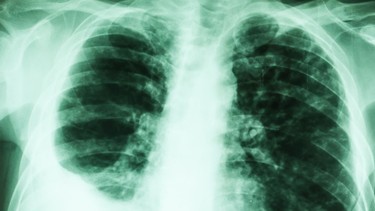

Xơ phổi là một bệnh lý nghiêm trọng và tiến triển mạn tính, có thể đe dọa trực tiếp đến tính mạng nếu không được phát hiện sớm và kiểm soát đúng cách. Đây không phải là bệnh truyền nhiễm, nhưng mức độ nguy hiểm của xơ phổi nằm ở chỗ tổn thương phổi diễn ra âm thầm, không thể hồi phục và ngày càng nặng theo thời gian.

Về bản chất, xơ phổi xảy ra khi các mô phổi lành bị thay thế dần bằng mô xơ cứng. Những vùng phổi này mất đi tính đàn hồi vốn có, khiến phổi không thể giãn nở bình thường khi hít thở. Hậu quả là khả năng trao đổi oxy suy giảm nghiêm trọng, cơ thể không được cung cấp đủ oxy để duy trì hoạt động của các cơ quan.

Một trong những biểu hiện nguy hiểm nhất của xơ phổi là khó thở tiến triển. Ban đầu, người bệnh chỉ cảm thấy hụt hơi khi vận động mạnh, leo cầu thang hoặc làm việc nặng. Tuy nhiên, theo thời gian, tình trạng khó thở có thể xuất hiện ngay cả khi nghỉ ngơi, khiến người bệnh luôn trong trạng thái mệt mỏi, kiệt sức và phụ thuộc vào oxy hỗ trợ.

Không chỉ dừng lại ở rối loạn hô hấp, xơ phổi còn có thể gây ra nhiều biến chứng nguy hiểm như tăng áp lực động mạch phổi, suy hô hấp mạn tính, suy tim phải do tim phải làm việc quá tải để bơm máu qua phổi bị tổn thương. Ở một số trường hợp, xơ phổi còn làm tăng nguy cơ phát triển ung thư phổi.